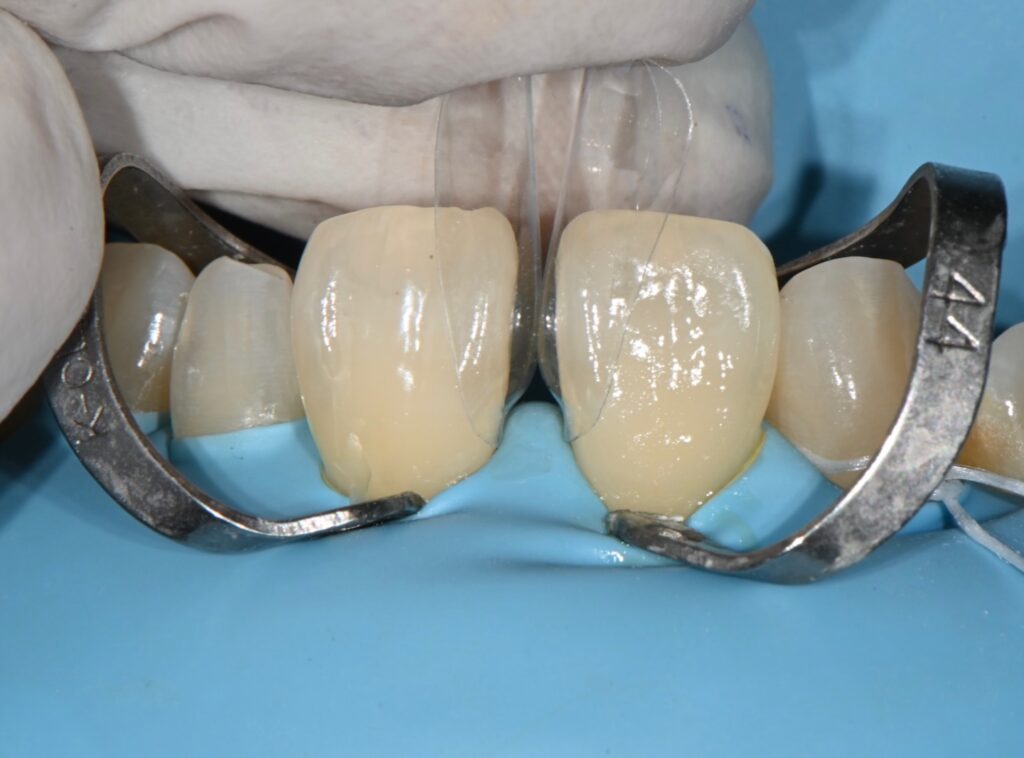

레진 치료의 첫번째 철저한 방습

레진 치료의 가장 중요한 부분은 방습인데요

침이나 수분에 굉장히 취약한 부분이기에

레진이나 라미네이트 모두 철저한 방습이 필수입니다

깨끗하게 처리한 후 러버댐으로 방습을 시행하였습니다

저렇게 클램프라는 고리로 치아에 거는 이유는

치아의 끝부분까지 자연스럽게 레진으로 충전하기 위해서입니다